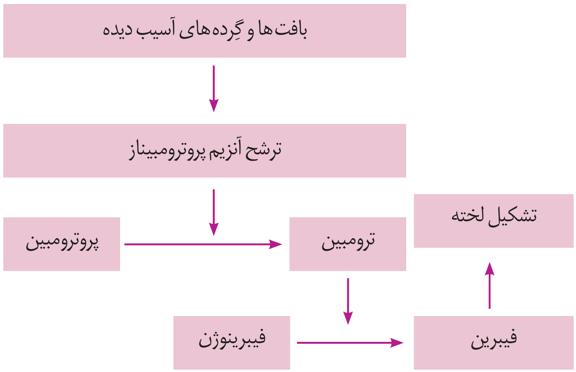

الف) مواد مفید موثر در روند انعقاد را دوباره به خون بازمیگرداند.

الف) موادی مانند یون کلسیم برای انعقاد ضروریاند. کلیه با بازجذب کلسیم به حفظ هم ایستایی آن در بدن و فرایند انعقاد خون کمک میکند.